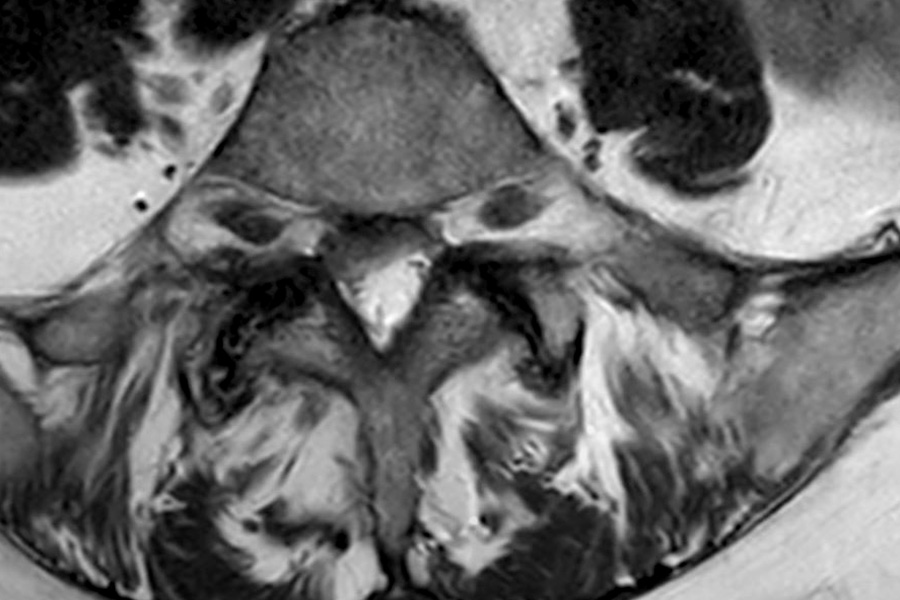

La paciente presentaba una estenosis de canal entre las vértebras L4L5 y L5S1. Esto le producía mucho dolor, empeorando su calidad de vida.

Durante la operación de estenosis de canal se procederá a abrir el ligamento amarillo, liberando el tejido neurológico completamente.